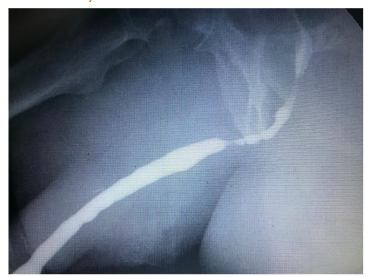

The urethral stent is a self-expanding steel mesh that opens the urethral lumen. It is a procedure under vision, outpatient, with little or no bleeding and does not require a urethral catheter, the patient urinates immediately after stent implantation. It can be considered as an alternative to the indwelling urethral catheter in selected patients with bladder outlet obstruction. It’s a very good option in elderly patients with benign prostatic hyperplasia, chronic retentionists and with high surgical risk with multiple pathologies and polypharmacy or who refuse surgery.